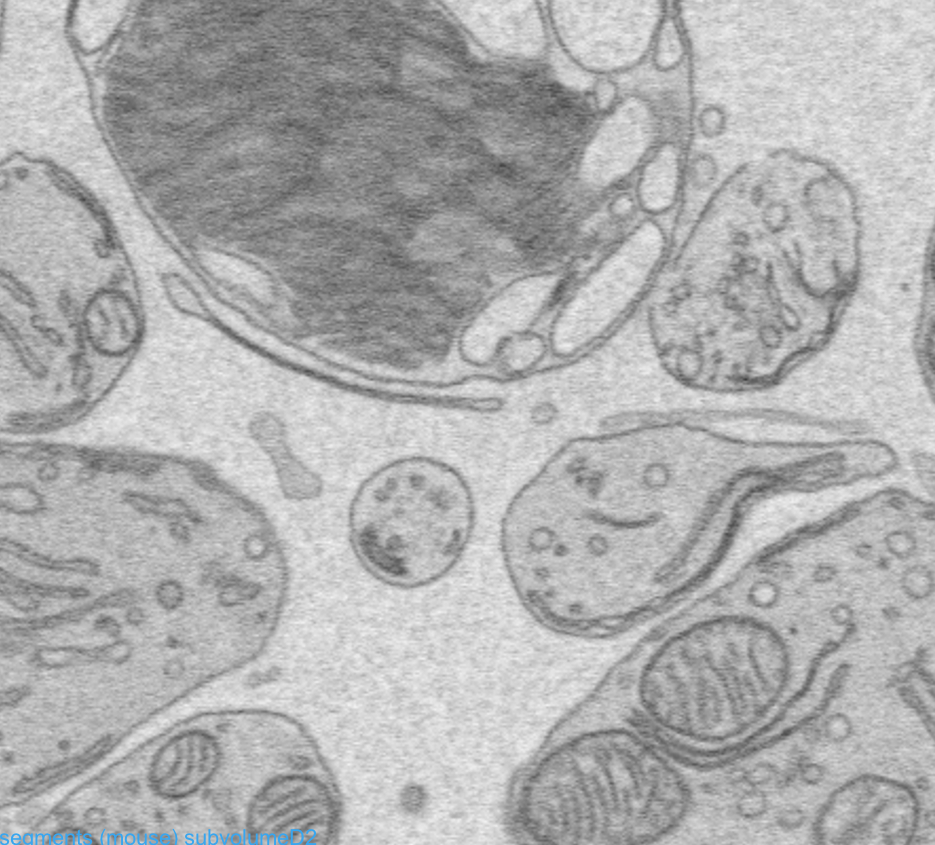

- FIB-SEM

セグメンテーションに時間がかかる…

・ AIディープラーニングで複雑なセグメンテーションも簡単に *

コントラストが同等で閾値での区別が困難な場合や、ポアバックの問題など、ディープラーニングを活用して省力化を実現します